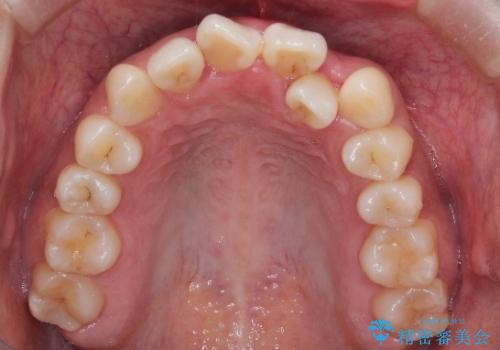

初診時の歯並びの状態としては、上下ともに全体に及ぶの中等度のがたつき(叢生)があり、全特に左上の前歯は1本だけ引っ込んでいる状態でした。

抜歯は行わず上顎の奥のスペースを利用して歯をスライドする方法の他に歯列弓の拡大やディスキング(歯と歯の間の隙間を作る処置)を行い叢生を改善しました。

歯の大きさの不揃いが原因の正中のズレは、ディスキング量を調整することで合わせました。